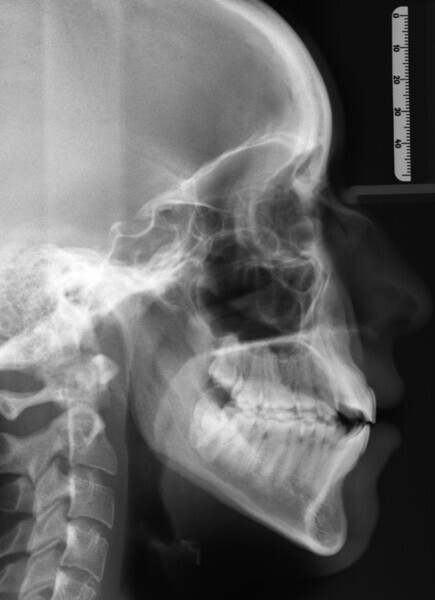

The 23-year-old dolichofacial female patient complained of not being able to chew properly. Facial examination showed a convex profile, an enlarged lower facial height, and a skeletal Class III malocclusion (Figs. 1–3). Intra-oral examination revealed an Angle Class III right subdivision malocclusion, anterior open bite, no overjet and a maxillary dental midline deviated about 3 mm to the right compared with the mandibular dental midline (Fig. 4). The panoramic radiograph confirmed previous extraction of the maxillary right first premolar and the presence of all four third molars (Figs. 5 & 6).

The treatment objectives included closing the anterior open bite, achieving a bilateral Angle Class I relationship and a proper overjet and overbite, correcting the midline discrepancies, and achieving a profile harmonisation. The treatment plan consisted of orthodontic camouflage treatment with asymmetric distalisation in three of the four quadrants using Invisalign aligners (Align Technology) and third molar extraction. The Invisalign Comprehensive package was chosen, and 63 pairs of aligners were used (Figs. 7–10). Each aligner was worn for 20 hours a day for one week each. The use of Class III elastics on both sides was indicated. Afterwards, ten refinement aligners were needed to improve the interdigitation on the right side (Figs. 11 & 12).

Although Class III elastics tend to extrude the maxillary molars and generate clockwise mandibular rotation, aligners allow us to prevent these complications, since we have better control over tooth movement, enabling us to counteract unwanted dental movements. In this case, an intrusion of the posterior teeth was planned, which would generate anticlockwise rotation of the mandible in an anticlockwise direction. This vertical control led to the closure of the anterior open bite and the reduction of the lower facial height, thereby improving the facial profile.

The total treatment time was 15 months. An Angle Class I relationship was established along with adequate anterior and canine guidance, establishing a functional occlusion. This not only ensures optimal masticatory function but also protects the teeth and the temporomandibular joint from excessive force. Maxillary and mandibular fixed retention were installed at the end of the treatment (Figs. 13–19).